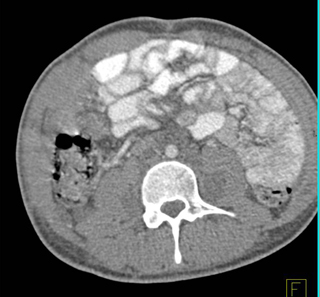

The best diagnosis in this case is?

lymphoma

neurofibromatosis

metastatic adenocarcinoma

MAI infection